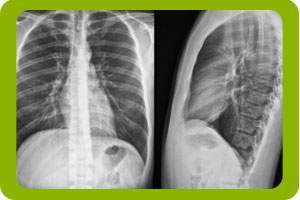

Los rayos X son invisibles a nuestros ojos, tienen una alta energía y una longitud de onda corta lo que los hace capaces de atravesar los tejidos.

Al pasar a través del cuerpo, los tejidos más densos, como los huesos, bloquean los rayos más intensamente que los tejidos de menor densidad como los pulmones.

De esta forma los rayos que pasan se plasman en la radiografía dejando en color obscuro las zonas que bloquearon el paso de los rayos.